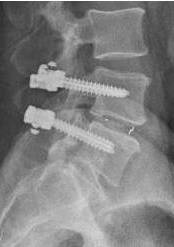

Nel trattamento di un solo spazio si può talora ricorrere alla tecnica "stand alone" (fig.10), ossia senza associazione di strumentazione con barre e viti.

• Figura 10